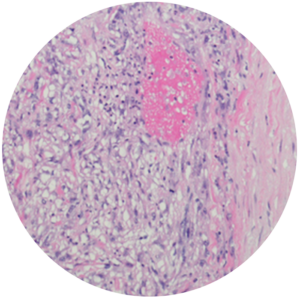

![Sarcomatoid Mesothelioma Prognosis]()

Sarcomatoid Mesothelioma Prognosis

Sarcomatoid mesothelioma is the rarest type, accounting for about 10-20% of cases. These spindle-shaped cells don’t stick together and spread rapidly, making them resistant to treatment. The life expectancy is 7 months, and the 2-year survival rate is 20%.